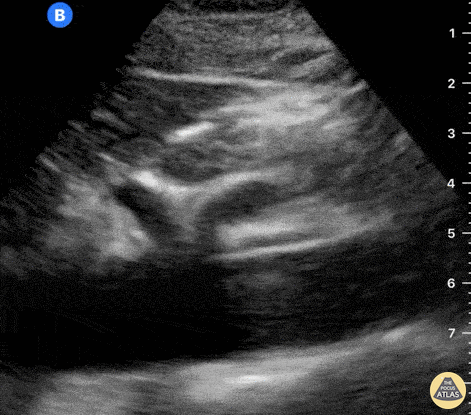

Aorta - Normal Celiac Trunk & SMA - Longitudinal

At the center of the screen, the proximal aorta can be identified by the emergence of the coeliac trunk and the superior mesenteric artery. This clip is taken at the subxiphoid level, longitudinal to the body’s axis, and with the probe marker oriented towards the head. Dr. Felipe Urriola P., Emergency Unit, Puerto Aysen Hospital, Chilean Patagonia.